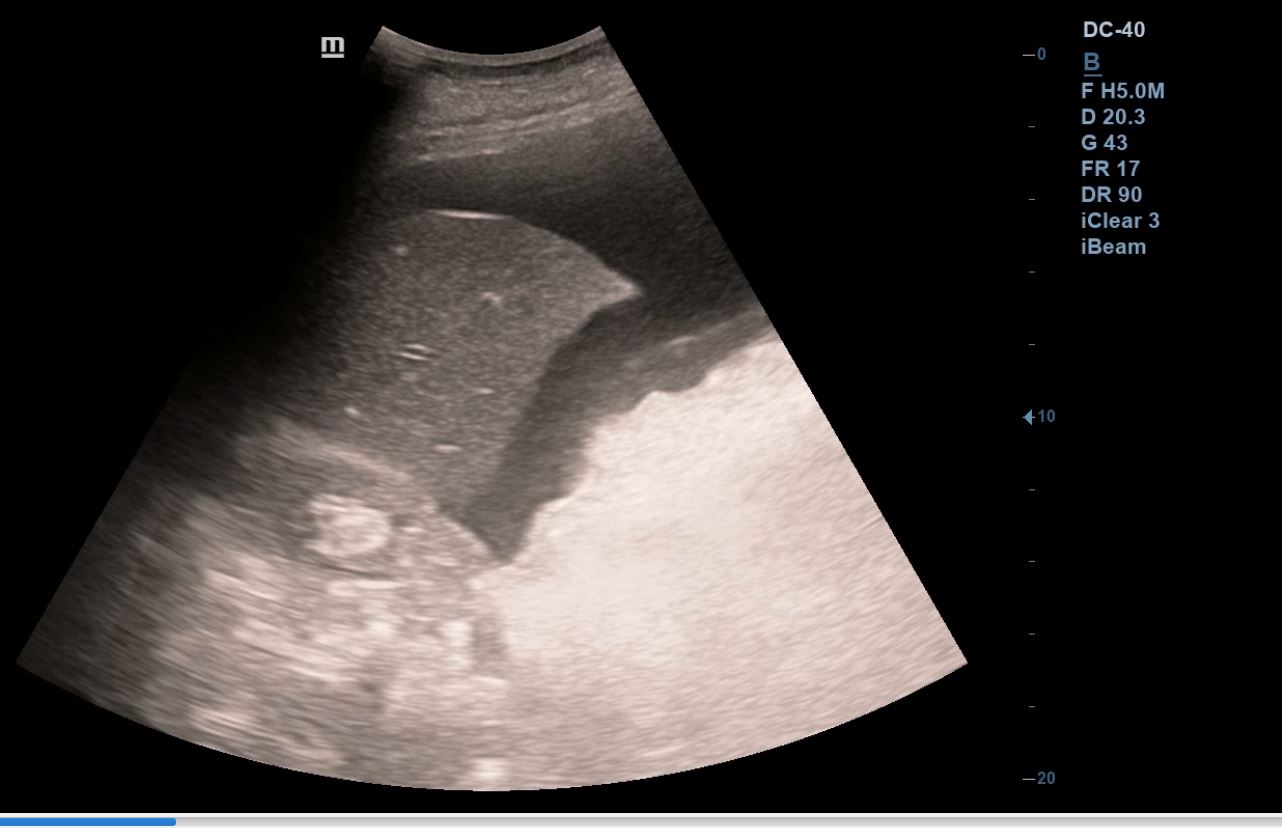

Se realiza ecografía clínica abdominal y pulmonar en la consulta, donde se visualiza líquido libre en espacio hepatorenal, esplenorenal y espacio de Douglas. En región pélvica presenta masa de aspecto heterogéneo con zonas anecoicas de 12 x 10 cm, con mapa color positivo. En la ecografía pulmonar presenta derrame pleural derecho.

En TAC toraco-abdomino-pélvico se describe «Gran masa pélvica de densidad heterogénea de 12 x 21 x 18 cm que sugiere neoplasia de origen ginecológico como primera posibilidad. Abundante líquido libre abdominal y pleural bilateral».